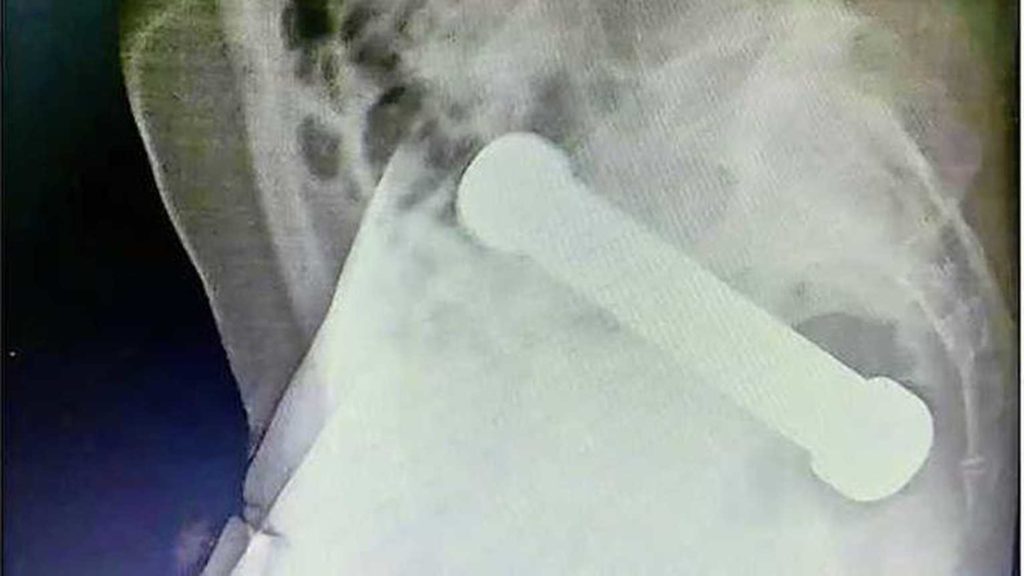

أظهرت الأشعة السينية كيف كان ذلك ممكنًا: اتضح أن لديه جسمًا طوله 20 سم في تجويف بطنه.

ووفقاً للأطباء ، فإن الرجل لم يتعاون جيداً أثناء المقابلة. ولذا قرروا إجراء أشعة سينية. في تلك الصور ، كان سبب الألم واضحًا بسرعة. كان وزنه في تجويف البطن 2 كيلوغرام. وكان طول ذلك حوالي 20 سم.